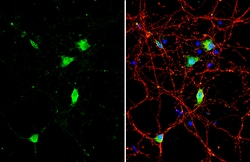

| Immunohistochemistry (Frozen), Immunohistochemistry (Paraffin), Western Blot, Immunocytochemistry | |